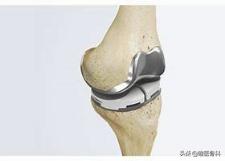

3) 对于严重骨关节炎的病人,膝关节置换手术将是合适的选择,通过手术可以将膝关节周围增生的骨刺去除,恢复平整的关节面和关节力线,进而实现疼痛的改善和功能的恢复。